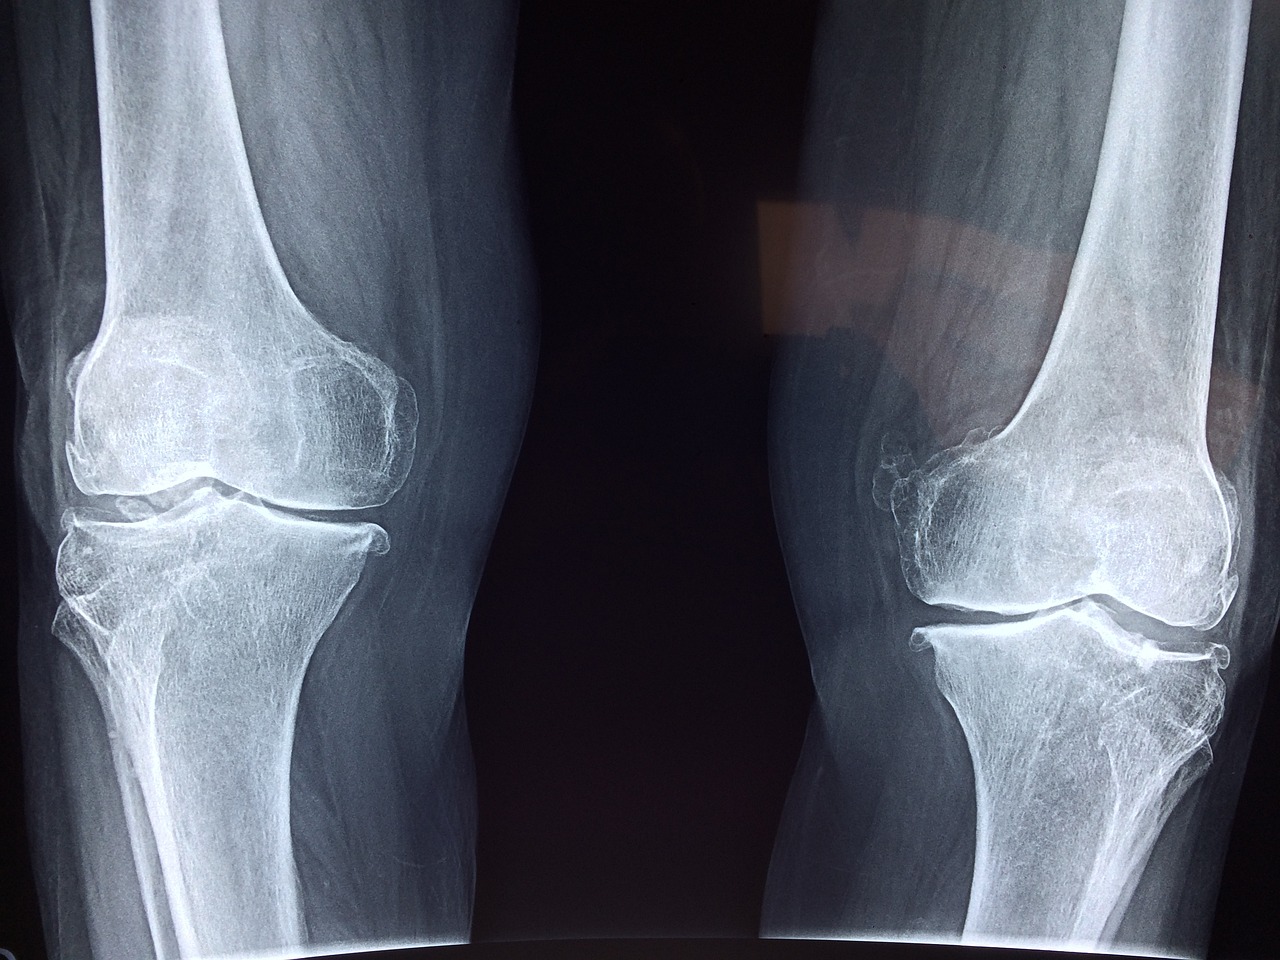

영양과 운동외에도 생활방식의 선택은 뼈와 관절의 건강에 큰 영향을 미칩니다. 가장 영향을 미치는 요인 중 하나는 건강한 체중을 유지하는 것입니다. 과체중은 관절, 특히 하체 관절에 스트레스를 가해 골관절염과 같은 질환의 위험을 증가시킵니다. 균형 잡힌 식단을 채택하고 규칙적인 신체 활동을 하면 체중 관리와 관절 건강 증진에 도움이 됩니다.